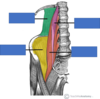

Red *

Deltoid

Innervation: Axillary nerve

Action: Flex, extend and abduct the shoulder

Red *

Supraspinatis

Innervation: Suprascapular nerve

Action: Abducts 0-15 degrees Assists deltoid 15-90 degrees

Blue *

Infraspinatus

Innervation: Suprascapular nerve

Action: Lateral rotation of arm

Green *

Subscapularis

Innervation: Upper and lower subscapular nerves

Action: Medial rotation of arm

Yellow *

Teres minor

Innervation: Axillary nerve

Action: Lateral rotation of arm